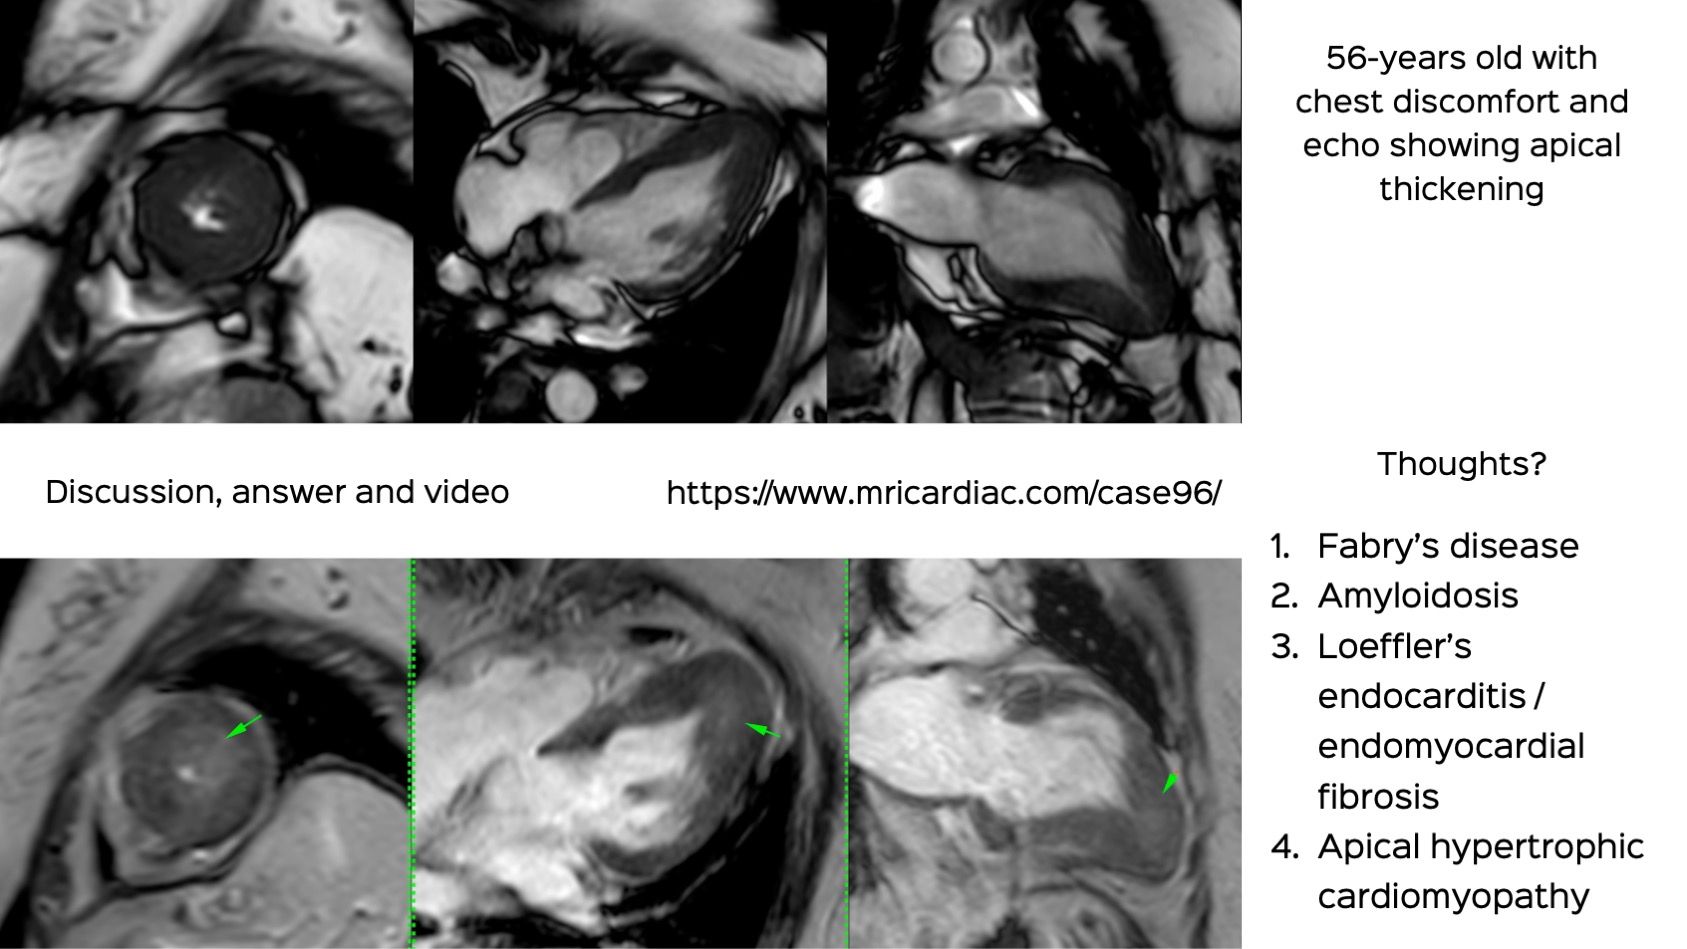

Case 96: The Ace of Spades

Apical HCM is a distinct entity that needs further understanding